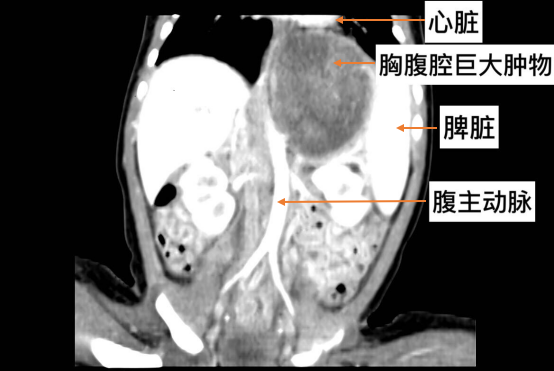

该名患儿母亲,怀孕7个月时产检发现胎儿左肾与左肺之间大小约6cm×5cm×4.5cm肿物待诊,家属慕名就诊于我院小儿外科李索林教授门诊,李索林教授考虑为巨大肺外型肺隔离症,建议出生后手术治疗。之后家属定期于我院产科和小儿外科门诊随访至孕足月。患儿39+5周于我院产科出生,生后即进入新生儿ICU进行生命支持,同时进行各项术前检查及准备。李索林教授团队于术前组织多次术前讨论,患儿的胸部CT显示,病变组织巨大,跨越胸腔和腹腔,压迫邻近脏器,同时腹主动脉多支血管走形其内及外缘,患儿胸腔及腹腔操作空间极小,如果单纯行胸腔或腹腔手术易造成失血量大,患儿体重仅3700g,大量失血极易造成患儿循环不稳定,影响生命,遂最终决定行胸腹腔联合手术。术中于脐部切口约2cm,经脐单部位同时置入腹腔镜头监视及操作钳,同时2cm的小切口也便于巨大病变肿物的取出,于右侧腹切开3mm小切口置入操作钳辅助手术,术后巧妙的经该切口放置腹腔引流管,避免了腹壁过多的手术瘢痕。腹腔镜下切除约1/3病变组织,随后患儿变换体位行胸腔镜手术切除剩余病变组织。手术历时约3个小时,术中出血不足5ml,充分保障了患儿内环境的稳定。同时胸腹腔巨大肿物仅通过腹壁及胸壁4个小切口即完成手术,避免了患儿胸腹壁巨大手术瘢痕,达到微创美观效果。